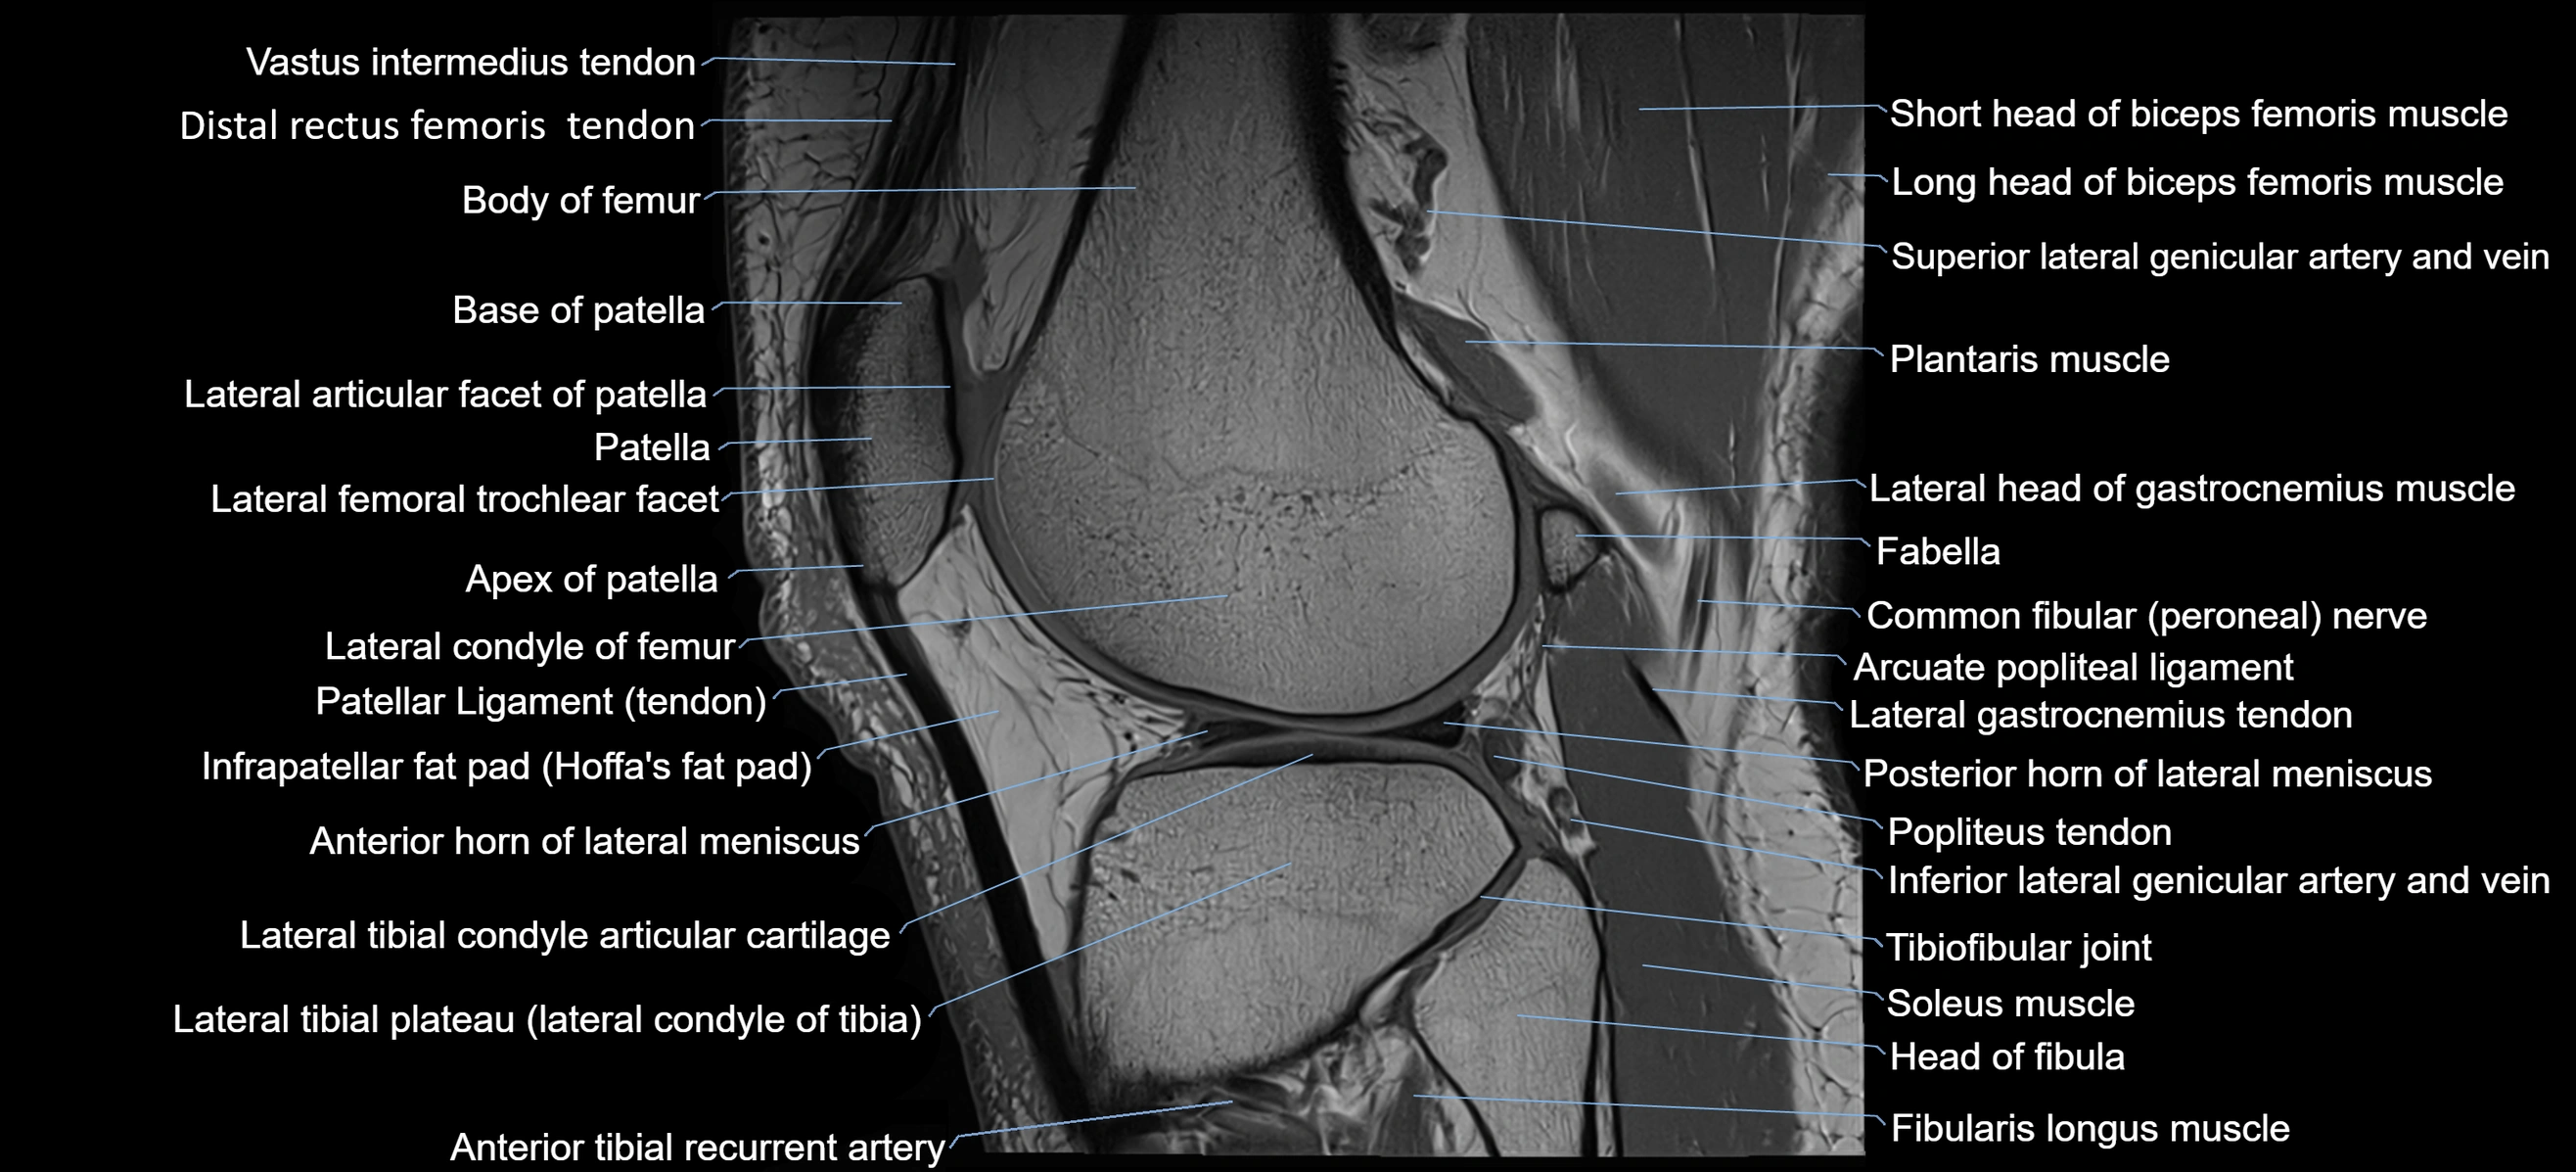

- Anterior horn of lateral meniscus

- Anterior root of lateral meniscus

- Apex of patella

- Arcuate popliteal ligament

- Base of patella

- Biceps femoris muscle (Short head)

- Body of femur

- Common fibular nerve

- Distal rectus femoris tendon

- Distal vastus intermedius tendon

- Fibularis longus muscle (peroneus longus muscle)

- Head of fibula

- Inferior lateral genicular artery

- Inferior lateral genicular vein

- Infrapatellar fat pad

- Lateral articular facet of patella

- Lateral condyle of femur

- Lateral gastrocnemius tendon

- Lateral head of gastrocnemius muscle

- Lateral meniscus

- Lateral tibial plateau

- Neck of fibula

- Patellar tendon (patellar ligament)

- Plantaris muscle

- Popliteus tendon

- Posterior horn of lateral meniscus

- Soleus muscle

- Superior lateral genicular artery

- Superior lateral genicular vein

- Superior tibiofibular joint

- Tibiofibular joint (proximal)